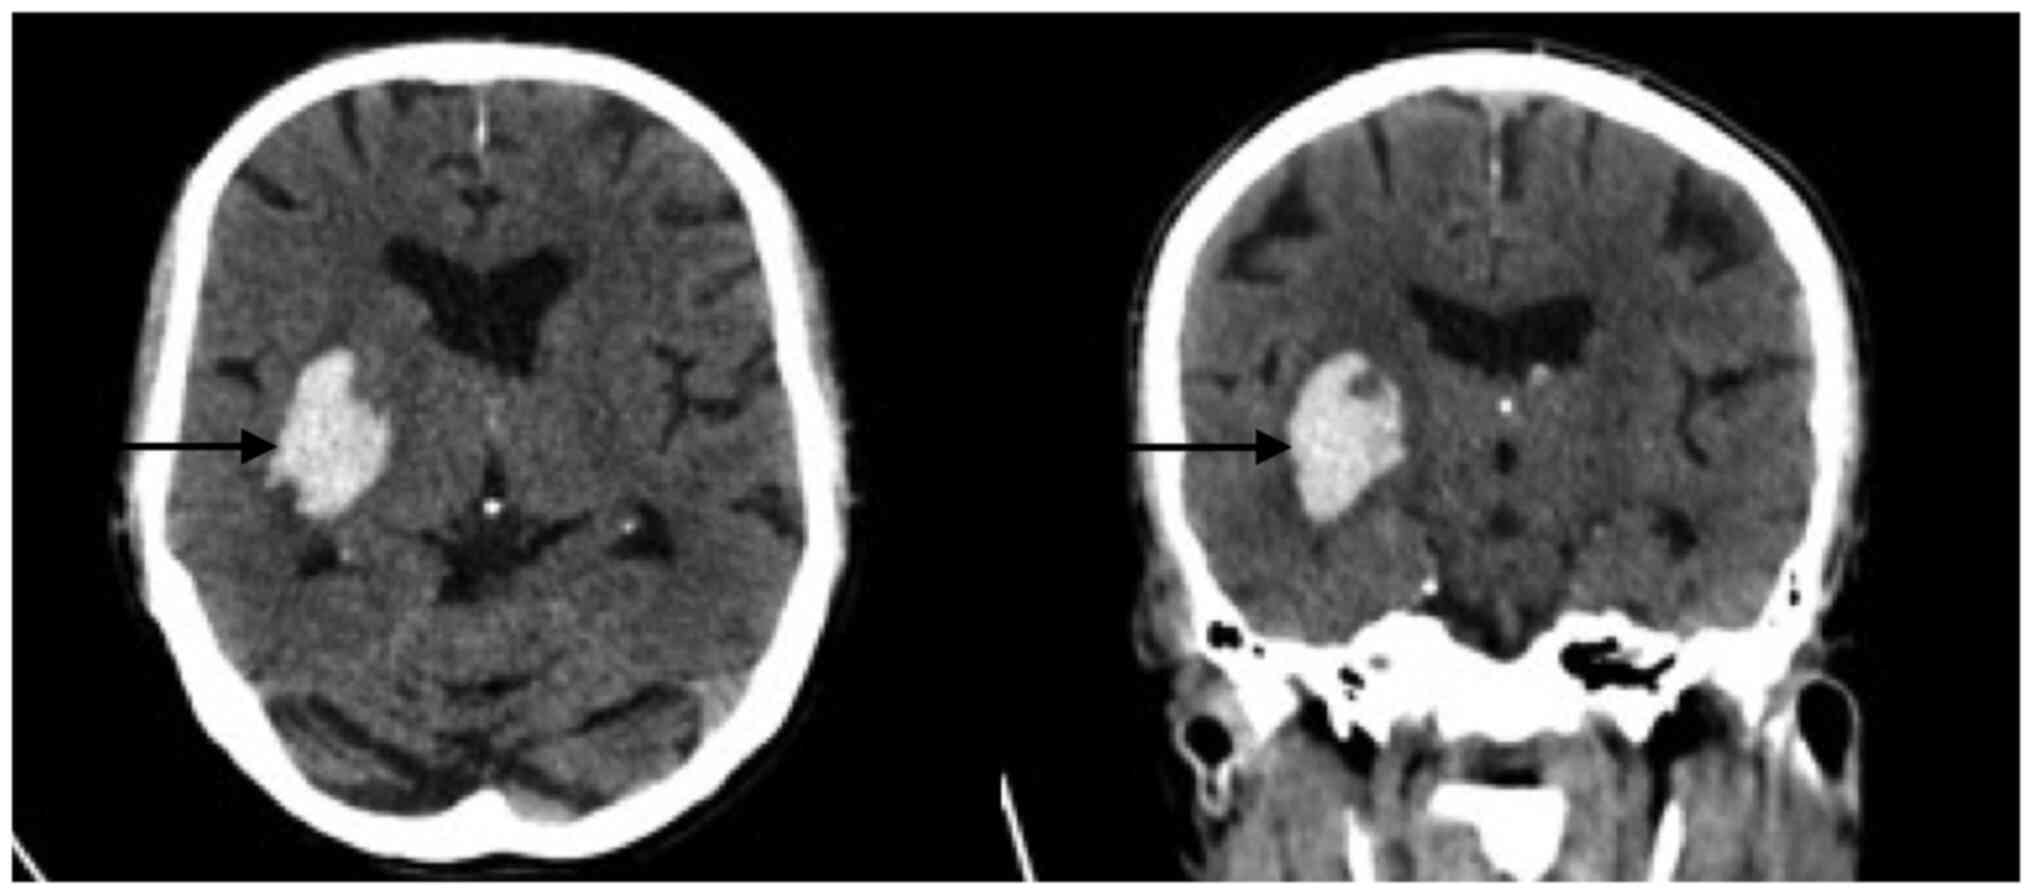

A 78-year-old male patient was transferred from a lower-complexity to a high-complexity hospital in August 2021 because imaging and hemodynamic services were unavailable in the former setting. At the lower-complexity hospital, the patient presented with weakness and decreased muscle strength in the left half of the body with 2 h of evolution, which was associated with dysarthria and deviation of the right labial commissure. The patient was admitted with elevated blood pressure (220/110 mmHg), for which 20 mg of labetalol was administered intravenously. An ECG was immediately performed, which revealed elevation of the ST segment, a situation that was managed pharmacologically as a myocardial infarction by administering 80 mg of atorvastatin and 300 mg of clopidogrel. Subsequently, the patient was transferred to a higher-complexity hospital, where it was observed that the patient neither had a history of angina or dyspnea, nor symptoms of a coronary syndrome. Fig. 1 presents ST-segment elevation in V1, V2 and V3 (acquired at the low-complexity hospital). Fig. 2 depicts ST-segment elevation in V3 and V4 (acquired at the high-complexity hospital) and Fig. 3 presents right temporal intraparenchymal hematoma with vasogenic edema and ventricular involvement (acquired at the high-complexity hospital).

Figure 3

Simple skull tomography upon admission. A right temporal intraparenchymal hematoma (arrows) with vasogenic edema and ventricular involvement of 1x30x40 mm was observed (on the left, an axial section is observed and on the right, a coronal section is present).

After 6 h, the patient was admitted to Hospital San Vicente Fundación (Rionegro, Colombia), a highly complex hospital (a hospital with the infrastructure, technology and specialists that allow it to provide the population with a health service that treats the most complex diseases), where the following vital signs were recorded: Blood pressure, 184/83 mmHg (hypertensive); heart rate, 52 beats per minute (bradycardia); respiratory rate, 22 breaths per minute tachypneic; and oxygen saturation, 97% (normal value). On physical examination, the patient was drowsy and oriented in three spheres. Muscular strength was 5/5 in the right half of the body and 4/5 in the left upper limb without alteration in sensitivity, aphasia or dysarthria. The patient denied symptoms including chest pain, angina, dyspnea, limitation in functional class, palpitations and previous cardio and neuromuscular events. Acute neurovascular syndrome was suspected, for which a simple skull tomography was performed, revealing spontaneous IPH of the right basal ganglion in the context of an acute cerebrovascular accident of hypertensive origin without any criteria for neurosurgical surgical intervention; furthermore, the patient did not require reversal of the administered antiplatelets. Fig. 4 reveals a right temporal intraparenchymal hematoma with vasogenic edema and ventricular involvement without any changes compared with the previous one. Fig. 5 suggests no akinesia or hypokinesia, but diastolic dysfunction and relaxation disorders are present.

Figure 4

Simple skull tomography (control at 24 h). A right temporal intraparenchymal hematoma (arrows) with vasogenic edema and ventricular involvement was observed without any changes compared with the previous one (on the left, an axial section is observed and on the right, a coronal section is present).